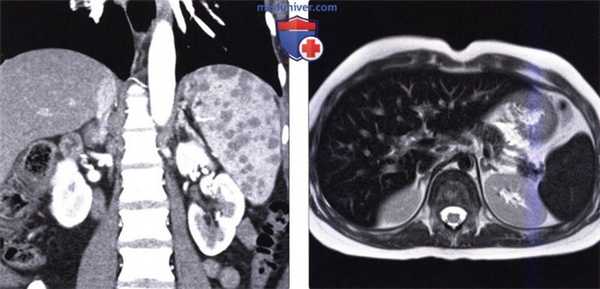

(Слева) На аксиальной КТ с контрастным усилением у наркозависимого пациента 29 лет (вводящего наркотики внутривенно), у которого возникли множественные гнойничковые поражения кожи наряду с болью в животе и повышением температуры тела, определяется гиподенсный очаг в селезенке (абсцесс).

(Справа) На аксиальной КТ с контрастным усилением у этого же пациента определяются множественные абсцессы в печени. Во время эхокардиографии были также обнаружены вегетации на клапане аорты, обусловленные эндокардитом (не продемонстрированы).

(Слева) На корональной КТ с контрастным усилением определяется умеренно выраженное увеличение селезенки с наличием множественных гиподенсных узлов в ее паренхиме. Позднее у этого же пациента была выявлена внутригрудная лимфаденопатия; при биопсии селезенки подтвердился саркоидоз.

(Справа) На аксиальной Т2 ВИ МР томограмме определяется выраженное снижение интенсивности сигнала от печени, селезенки и костного мозга у пациента с гемосидерозом, обусловленным множественными переливаниями крови.